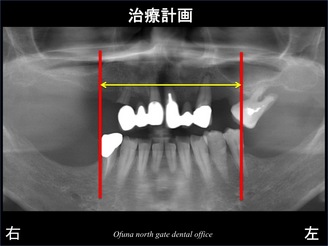

初診時のレントゲン写真が以下になります。

以下のレントゲン写真の×印は抜歯が必要な歯です。

どれくらい骨吸収が進行しているかを分かりやすくするために、

骨の状態を線で書いたのが以下になります。

青線が骨吸収を起こす前の骨の位置です。

赤線は、現在の骨の位置です。

骨が吸収してしまったのが分かるかと思います。

緑線は上顎洞です。

上顎洞(緑線の上方)は空洞です。

骨ではなく、穴が開いているのです。

黄色線は、鼻腔です。

この線の上も空洞です。

骨吸収が大きく、インプラントを埋め込むのが難しいのが分かるかと思います。

赤線の内側の範囲内でインプラントを埋入する計画になりました。